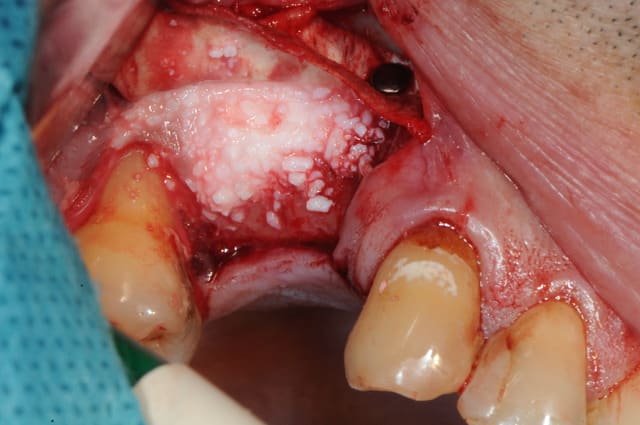

en attendant voici un des deux sinus de ce matin.

MP3 ( chez Pred) en comblement et ROG avec membrane et pins pour palier la forte concavité vestibulaire.